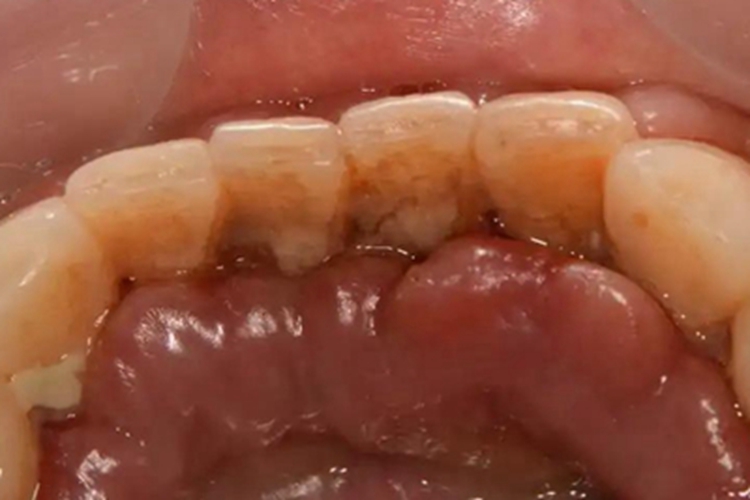

急性白血病侵犯口腔,可导致牙龈高度增生、肿胀,牙龈组织较之前隆起明显,逐渐覆盖牙齿,而且容易破溃出血,是急性白血病重要的体征之一。

该病主要是由于骨髓正常的造血功能受到抑制,患者外周血中中性粒细胞缺乏,自身的免疫力下降,从而容易出现细菌的继发感染,导致牙龈组织出现肿胀。